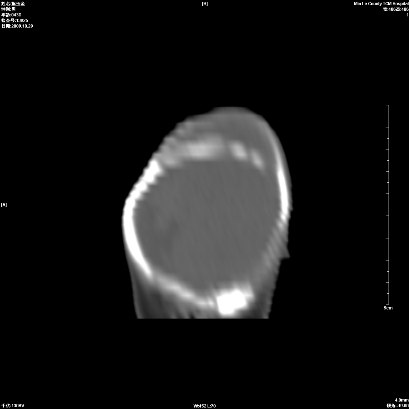

标题: PED2966:男性,42天。右顶部包块。考虑轻度脑-脑膜膨出(出生 [打印本页]

标题: PED2966:男性,42天。右顶部包块。考虑轻度脑-脑膜膨出(出生

慢性骨膜下血肿(骨化)

支持右顶部慢性骨膜下血肿(骨化)。

是骨膜下血肿机化,而不是硬膜下血肿机化,请大家注意。

右侧顶部慢性骨膜下血肿(机化、钙化)。